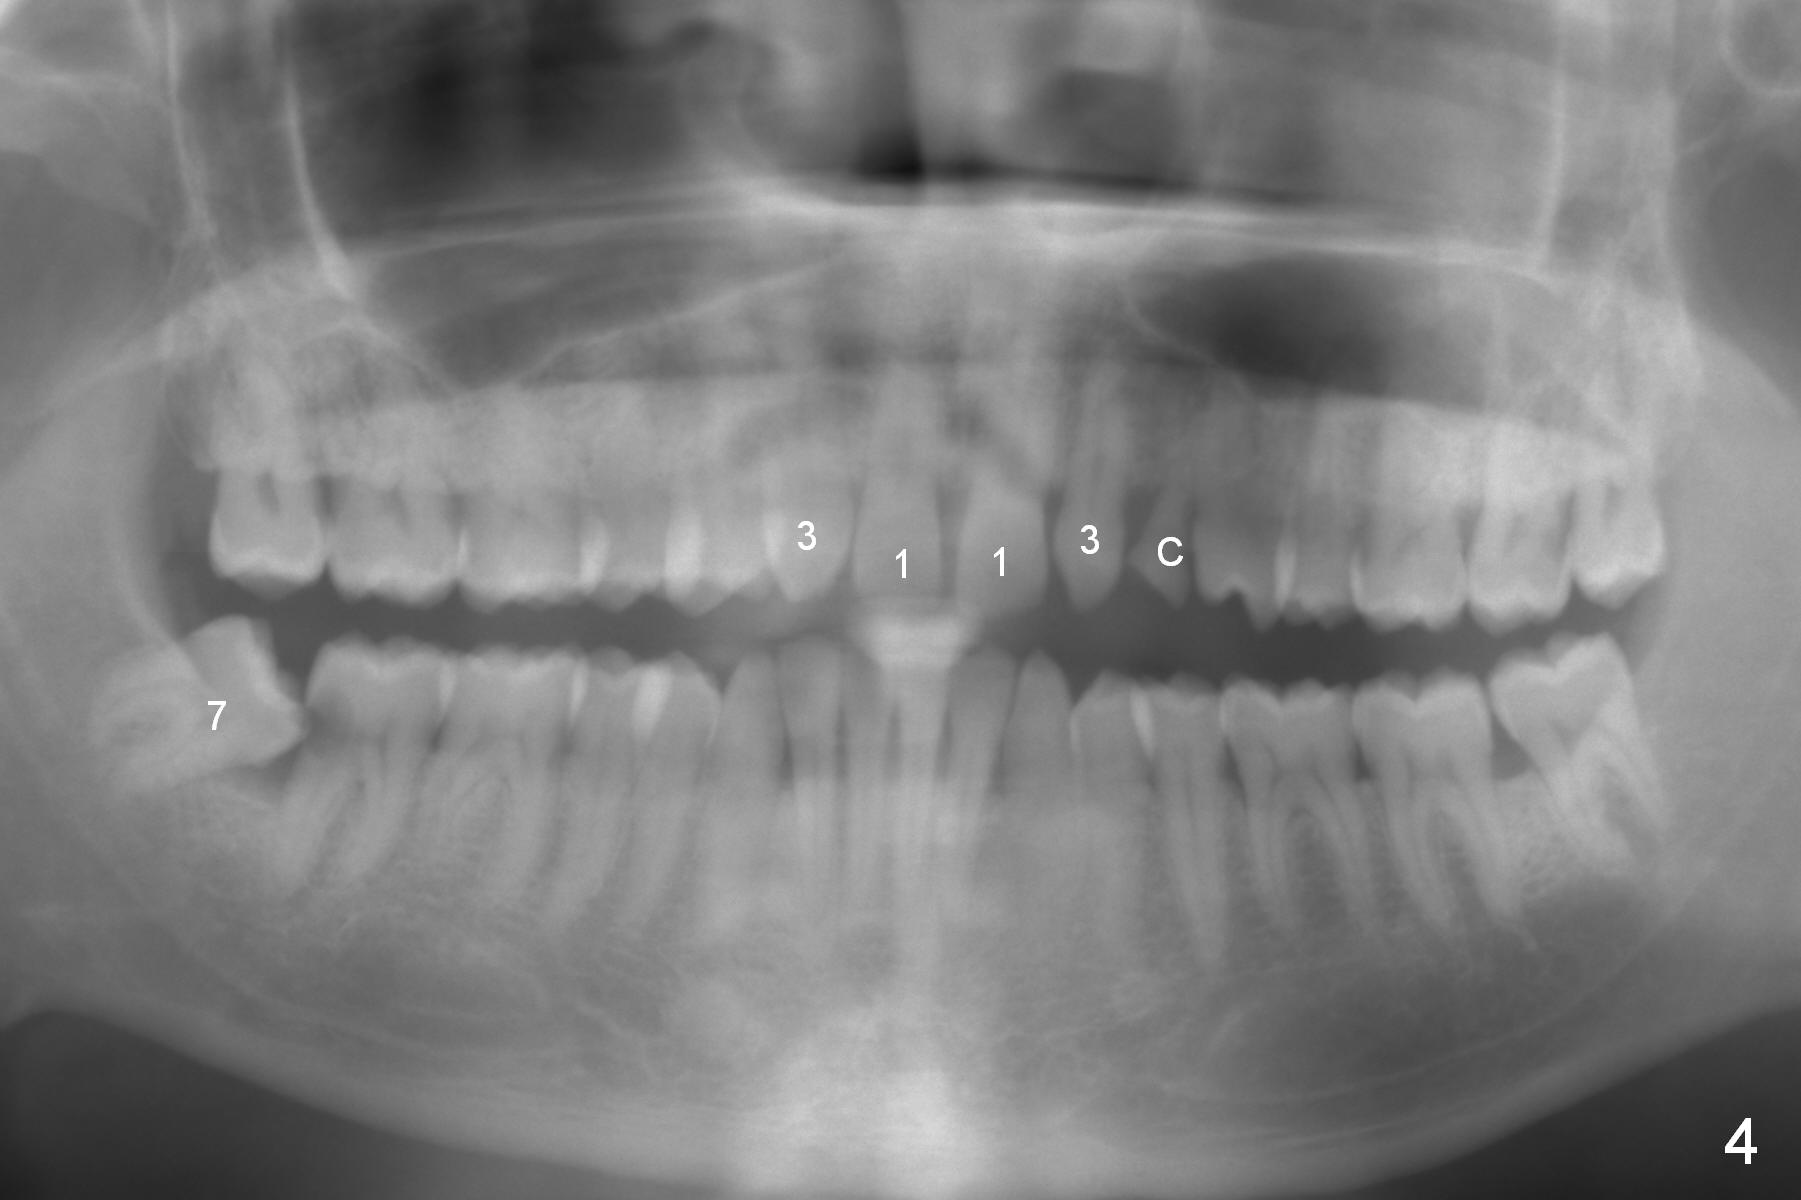

A 38-year-old man has congenitally missing laterals (Fig.1,2) with retention of a deciduous canine (Fig.2,3 C). UL 4 (upper left 1st bicuspid) rotates (Fig.3). LR7 has been extracted (Fig.4).